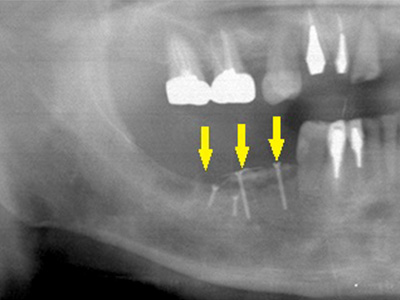

患者様の智歯の辺りから、患者様ご自身の骨を採取し、移植した後のレントゲン写真です。

採取した骨片を、小さなチタン製のスクリューで固定してあります。

これが遊離自家骨移植術です。 -